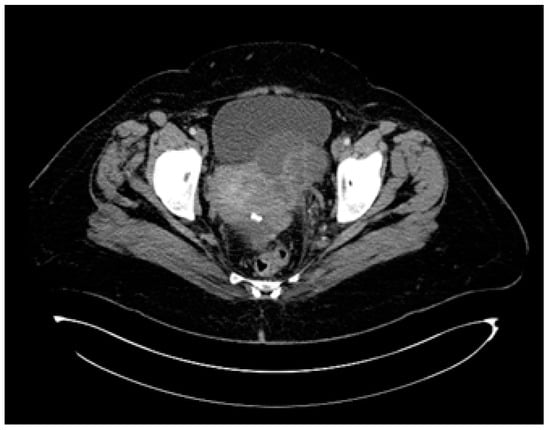

2.1.3. Examinations and Investigations

2.1.4. Diagnosis